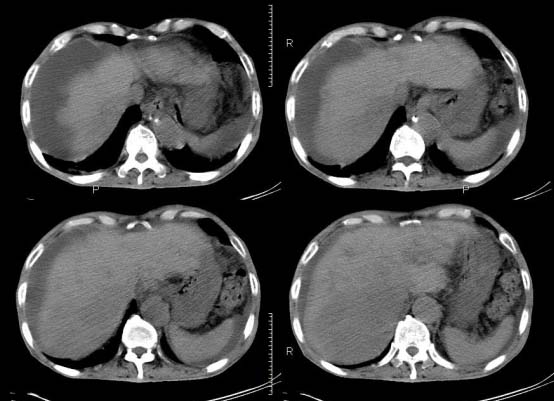

以下是引用杀毒软件在2010-3-30 18:11:00的发言:[br]考虑---hcc侵犯侵犯周围组织〔胰腺、胆管、肠系膜上动静脉〕伴门脉、下腔静脉癌栓形成、动-静脉瘘、肝门、腹腔动脉周围淋巴结转移可能性大、腹水。

以下是引用pujunzhi在2010-3-31 8:45:00的发言:[br]支持 肝癌并多发肝内转移,胰头、肝门、腹腔动脉周围淋巴结转移,下腔静脉癌栓形成,肝硬化、腹水。

以下是引用jsgdoctor在2010-3-30 20:42:00的发言:[br]考虑---hcc侵犯侵犯周围组织〔胰腺、胆管、肠系膜上动静脉〕伴门脉、下腔静脉癌栓形成、动-静脉瘘、肝门、腹腔动脉周围淋巴结转移可能性大、腹水。